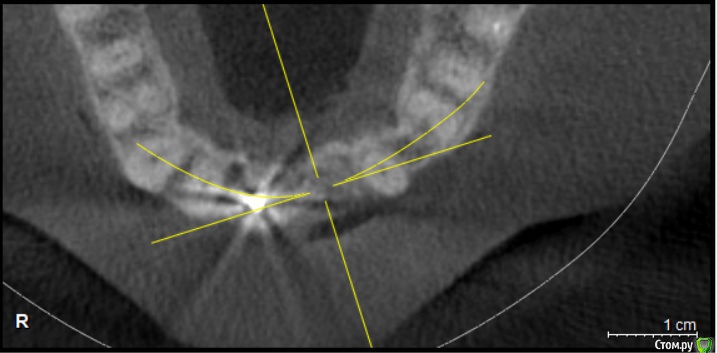

Kazankov.Egor Опубликовано 24 мая, 2018 Автор Поделиться Опубликовано 24 мая, 2018 Что смущает?Толщина стенок после планируемой имплантации, например, планирую поставить 3.3, получается, окружающей кости по 1мм, сколько такое простоит? Ссылка на комментарий

Nazim_NV86 Опубликовано 25 мая, 2018 Поделиться Опубликовано 25 мая, 2018 Доктор. Какая у вас хирургическая практика за плечами? По вашим КТ проблем ноль. Туда и 3,5 закрутить легко. Ссылка на комментарий

Evikrol Опубликовано 25 мая, 2018 Поделиться Опубликовано 25 мая, 2018 Я бы ставил подальше от нёбного канал, чтобы шахта была на уровне зенита планируемой реставрации, там и кости наверное больше, ну и отслоится хорошо чтобы видеть вестибулярную стенку и не перфорировать Ссылка на комментарий